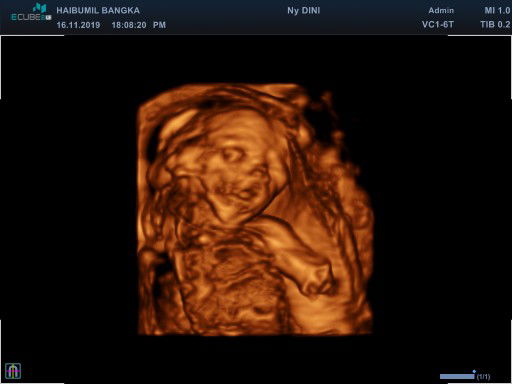

Sharing USG di haibumil.id Bangka

Hai bunda.. tadi malam aku habis USG nih.. aku usg di Haibumil.id cabang Bangka.. Alhamdulillah dokternya baik di jelasin hasil USG nya,.. Dan alhamdulillah dedebay nya sehat dan baik keadaannya mulai dari air ketubannya cukup, berat dan ukurannya, ari ari nya, jantungnya.. dan sudah masuk minggu ke 20.. sayangnya dedebay ini alhamdulillah aktif bgt sampai susah bgt mau di lihat wajahnya.. sekalinya dapet gerak terus dedenya.. Oh ya biayanya 200rb di bulan November untuk weekend, kalau weekday 150rb, dengan biaya tersebut sudah termasuk konsultasi, USG 2D, USG 4D, dan CD foto hasil USG. Haibumil.id ada beberapa cabang bisa di cek di Instagram @Haibumil.id Pertama kali USG 4D seneng bgt karna terlihat nyata, apalagi pas mau liat wajahnya yg ditutupin tangannya terus dia senyum.. kamu mau kasih surprise ke mama papa ya sayang .. alhamdulillah Bahagia dan alhamdulillah Bersyukur dengan karunia Allah SWT.. ? ☺ sehat sehat terus ya sayang ? ? Hallo teman teman bunda, coba tebak aku ya.. ???